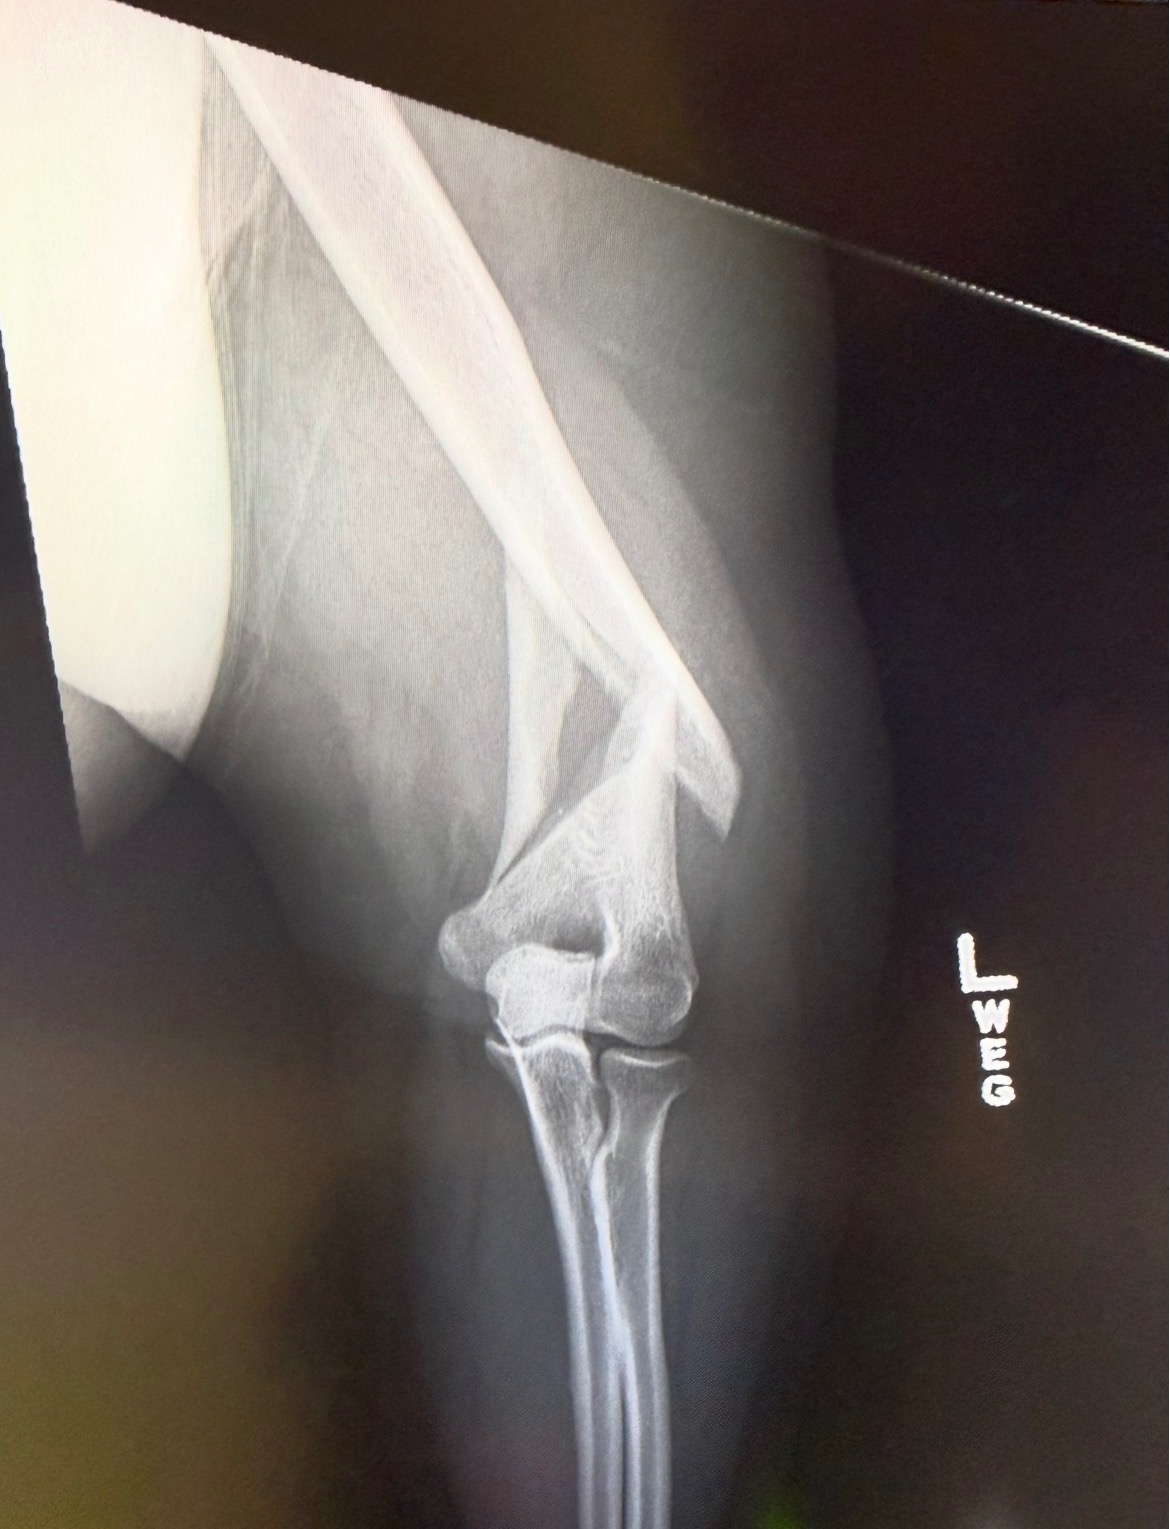

I now sport a broken arm due to a slip and trip on some stairs. I tried to catch myself on the railing, instead, my arm got caught but my body kept falling. After a trip to the ER for some X-rays, they gave me the news, broken humerus right above the elbow.

I am looking for assistance in paying for the bills that I have and will be coming my way; with surgery on the horizon, an ER bill or 2, and my monthly bills that I cannot pay as I am unable to work. Any assistance you can help with would be greatly appreciated. I know the amount looks like a lot but anyone who has had a medical emergency recently can attest these bills can get expensive and one of the doctors explained that getting metal in your body isn’t cheap.